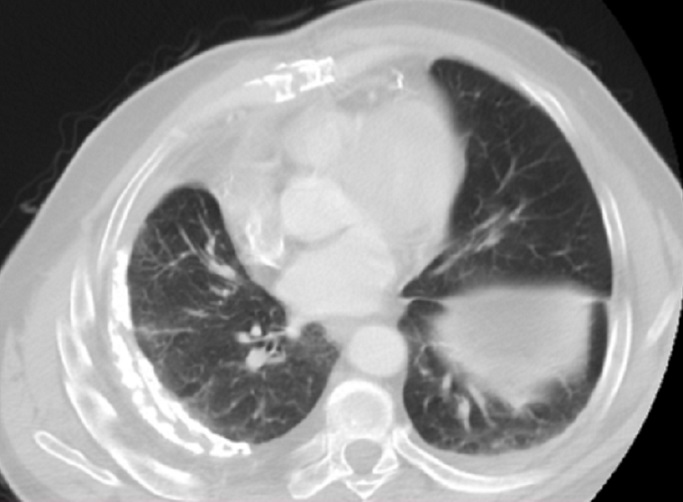

Mệme cas en coupe TDM axiale

avec aspect radiologique en plaque diffuse

hyperdensite de la plevre du poumon droit . Poumon

droit est en un peu de restrictive par la lesion de

tuberculose |